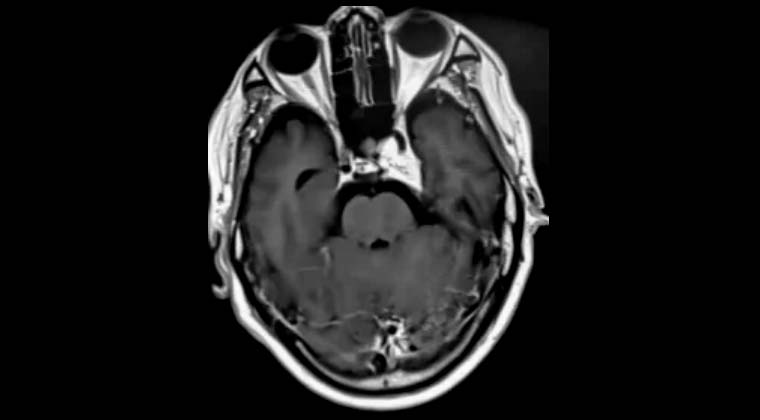

③ Случай 3:

Пациент: мужчина, 65 лет

Кавернозная гемангиома кавернозного синуса

Рисунок 1: 10.06.2020 Планирование лечения Гамма-ножом

Рисунок 2: 06.01.2021, через 6 месяцев после лечения Гамма-ножом очаг значительно уменьшился